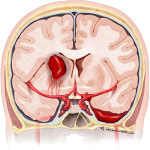

- Aneurysm ruptured

An aneurysm is a balloon-like bulge of an artery wall. As an aneurysm grows it puts pressure on nearby structures and may eventually rupture. A ruptured aneurysm releases blood into the spaces around the brain, called a subarachnoid hemorrhage, a life-threatening type of stroke. Treatment focuses on stopping the bleeding and repairing the aneurysm with clipping, coiling, or bypass.